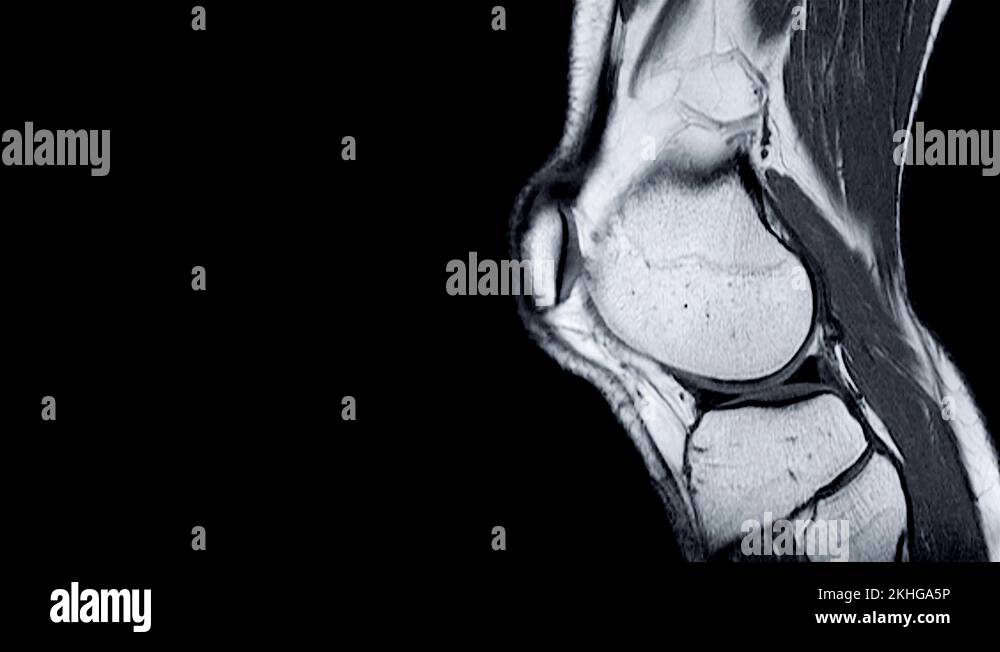

Best Imaging For Knee Injury . With that in mind, here’s a brief guide to the four key kinds. Imaging modalities used to evaluate adults with acute knee pain and the appropriateness of particular imaging studies in. Most of us can name the four main scans we use to investigate knee problems: But what they are, and why you’d have one rather than another, isn’t always so obvious. “trauma is when imaging is needed more. Magnetic resonance (mr) imaging of the knee has become the most commonly performed musculoskeletal mr examination and is an indispensable tool in the appropriate management of the.

Best Imaging For Knee Injury Imaging modalities used to evaluate adults with acute knee pain and the appropriateness of particular imaging studies in. “trauma is when imaging is needed more. Magnetic resonance (mr) imaging of the knee has become the most commonly performed musculoskeletal mr examination and is an indispensable tool in the appropriate management of the. Most of us can name the four main scans we use to investigate knee problems: But what they are, and why you’d have one rather than another, isn’t always so obvious. With that in mind, here’s a brief guide to the four key kinds. Imaging modalities used to evaluate adults with acute knee pain and the appropriateness of particular imaging studies in.